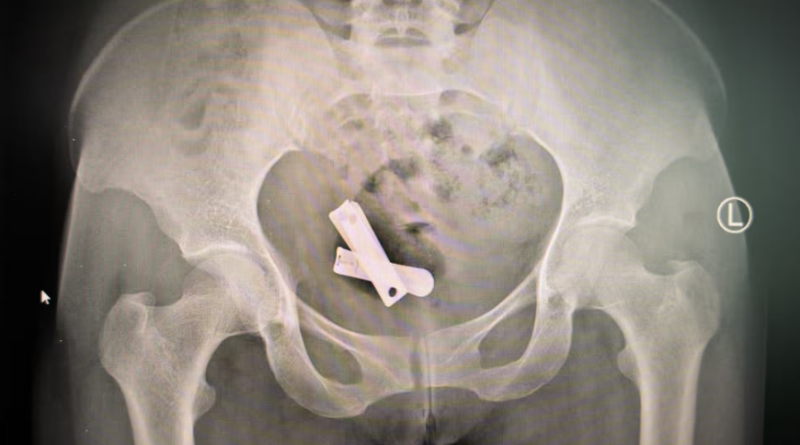

The objects, revealed by X-ray and surgically extracted by doctors more than two years later, were forced inside Tseneat as she lay unconscious after being gang-raped by six soldiers.

She is one of tens of thousands of Tigrayan women subjected to the most extreme forms of sexual violence, in attacks designed to destroy their fertility. Medical records and X-rays obtained by the Guardian and reviewed by independent medical specialists show a pattern of cases where women have had foreign bodies forced into their reproductive organs, including nails, screws, plastic rubbish, sand, gravel and letters. Under international law, it is genocide to destroy fertility or prevent births with the intention of wholly or partly destroying an ethnic group.

After removing the materials visible through her cervix, the staff performed X-rays to check for more foreign bodies. The image they produced is difficult to comprehend: at the centre of Tseneat’s uterus, between her hip bones, lies a pair of metal nail clippers. When they were removed, they were rusting, says Sister Roman, who treated her.

At a clinic in Mekelle, a team of nuns who provided medical care during the war maintained a single, locked cupboard where they kept a cache of evidence of the crimes against these women: X-rays, medical records, and even the objects themselves. “These foreign bodies are documented and also held in our storage – a lot of foreign bodies, anything, either plastics, metal objects, anything around them are introduced into their reproductive organs,” says Sister Mulu, who led the clinic. She leafs through X-rays, pulling out imaging of yet another abdomen – bisected by a sharp, curved metal spike and a thick bolt.

For the women who survived the insertion of objects, living with this kind of foreign body means “severe and long-lasting adverse health consequences and injuries”, says Dr Rose Olson, an internal medicine specialist and instructor at Harvard medical school, who has reviewed and commented on X-rays from the cases.

“If the object was inserted into the vagina and it was done so in a very forceful manner, it could certainly lead to a perforation or break through the tissue and then enter your abdominal cavity, and that would probably lead to very severe illness and injury,” she says.

The objects could easily remain there for years, Olson says, but would put the women at extremely high risk of “pelvic inflammatory disease, or inflammation which can lead to things like infertility and scarring, chronic pelvic pain and fistulas.”

“For someone who’s 20 or 30 years old, a lifetime of infertility, a lifetime of chronic pain, a lifetime of post-traumatic stress disorder that’s untreated, it’s very severe.”

Cover photo: In attacks designed to destroy fertility, foreign objects such as these nail clippers, were inserted into women’s wombs, usually following rape. Photograph: Ximena Borrazas